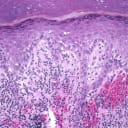

Alle 3 Bilder ansehenEine Stanzbiopsie der linken zweiten Zehe zeigt sowohl ein oberflächliches als auch ein tiefes perivaskuläres entzündliches Infiltrat, das vorwiegend lymphozytär ist, eine oberflächliche Hautblutung und eine lichenoide Gewebereaktion bzw. Interfacedermatitis (Abb. 4-6).

Stanzbiopsie

Grundlage für die Diagnose bildeten die Biopsieergebnisse, die lokale entzündliche Veränderungen (perivaskuläre lymphatische Infiltrate assoziiert mit papillärem Hautödem und epidermaler Spongiose) zeigten, die typisch für primäre Frostbeulen sind. Die Pathophysiologie ist noch kaum verstanden, sie scheint aber mit einer erhöhten kutanen Vasoreaktivität einherzugehen, die zu mikrovaskulären Verletzungen und einer daraus resultierenden Entzündungsreaktion führt.